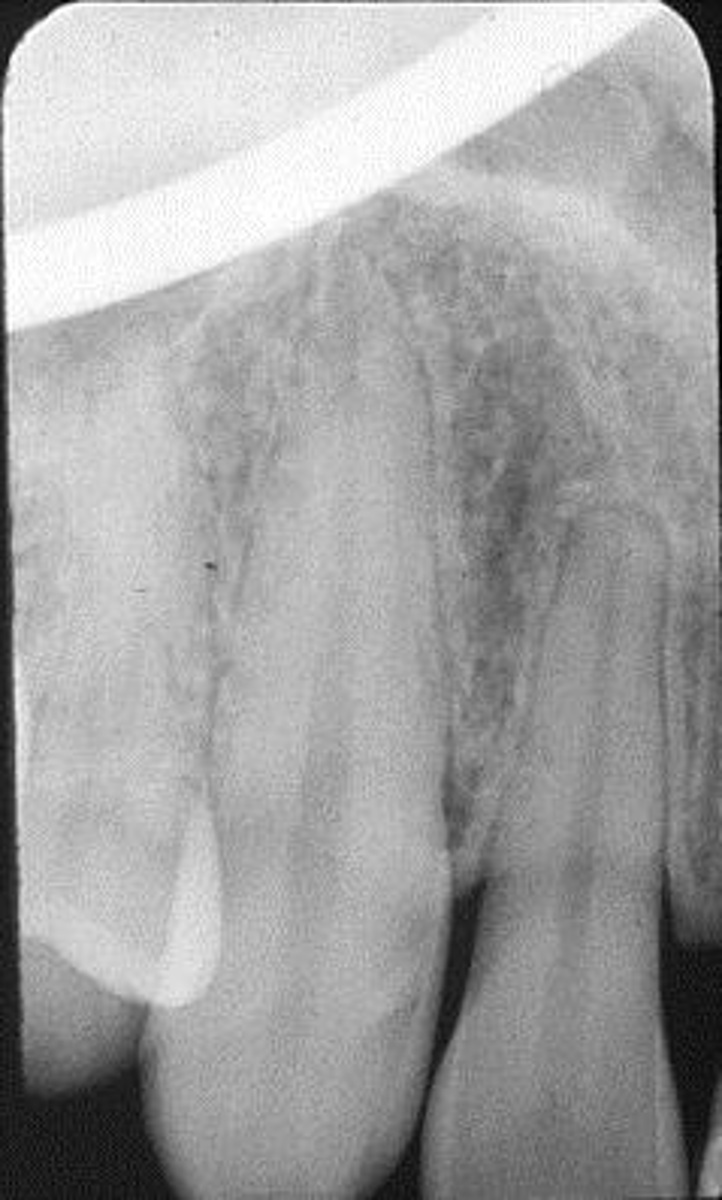

Elongated, vertical angulation, film holder (metal bar)

What is this error?